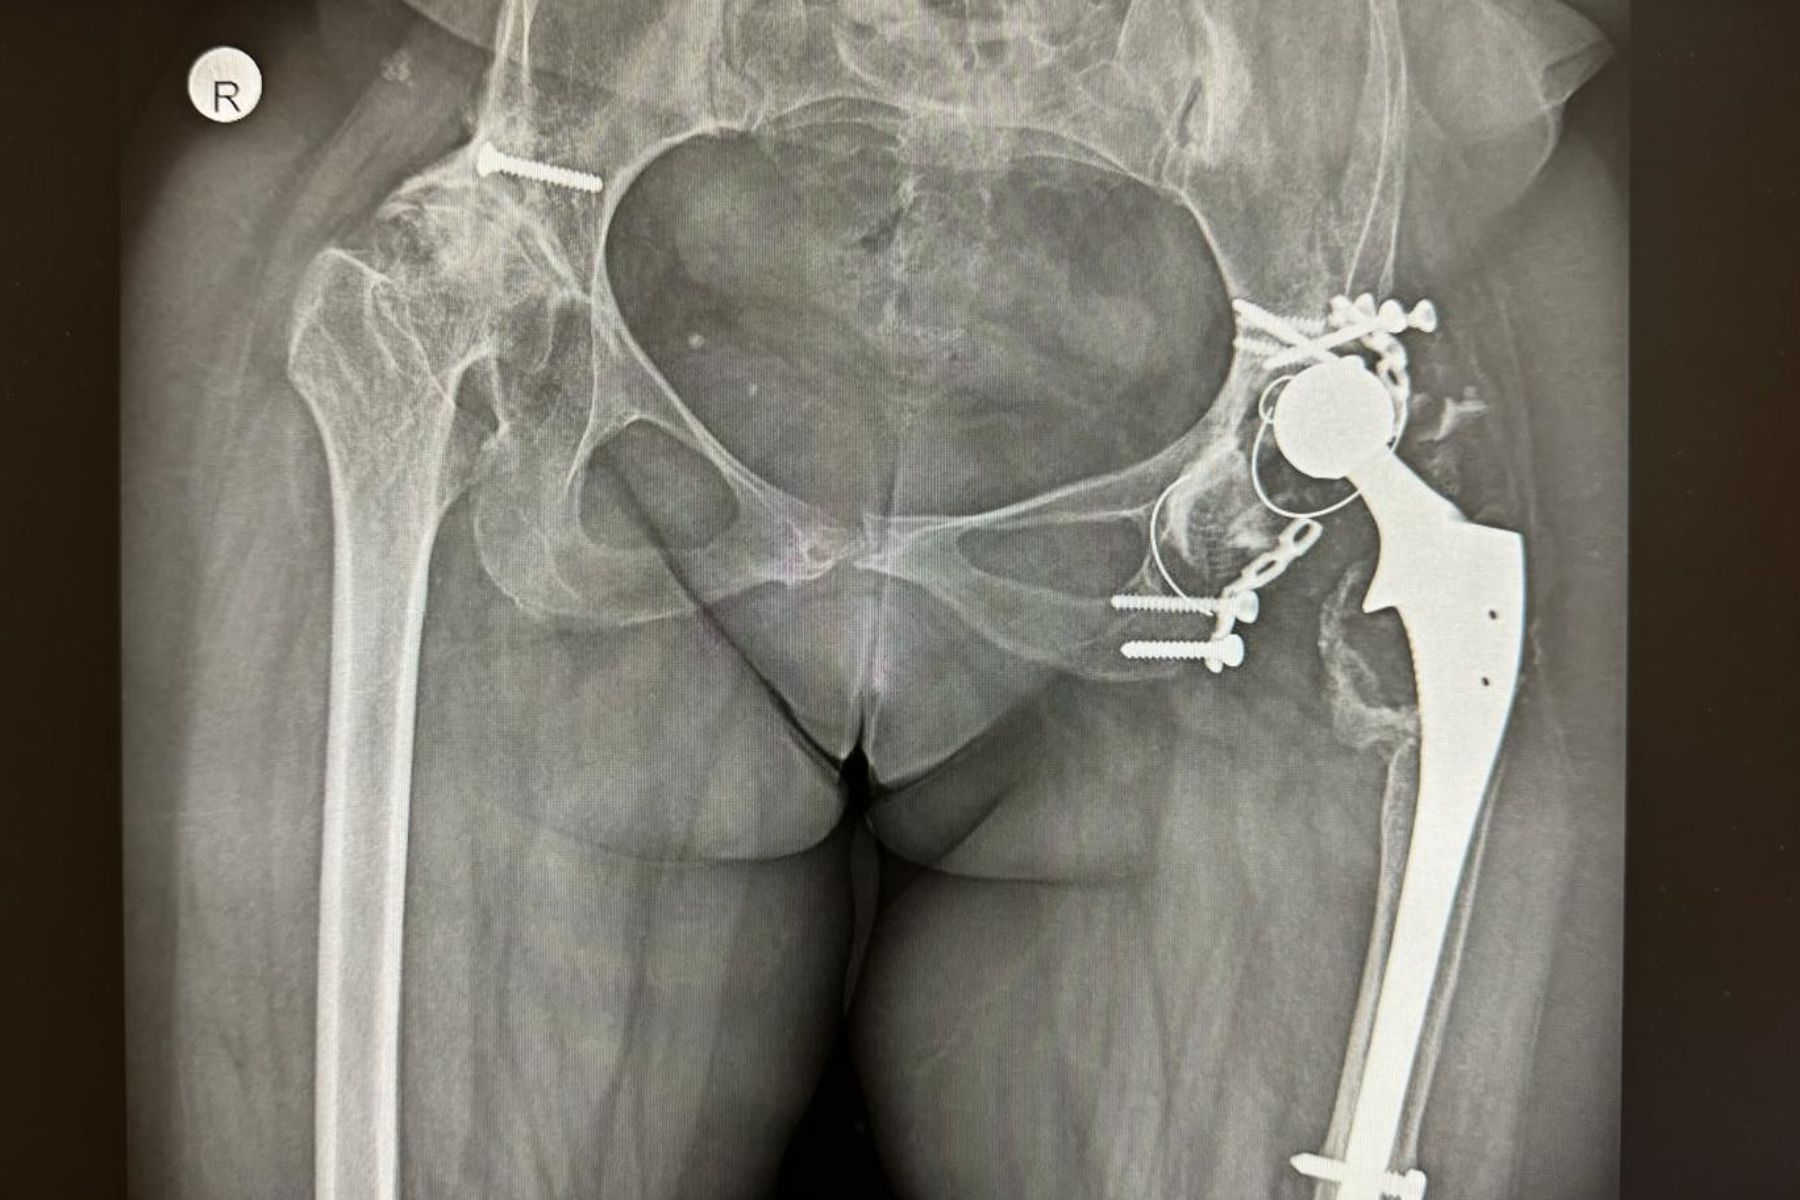

ORTOPEDIE-TRAUMATOLOGIE - Dr. Chirea Marius: Revizie complexă a protezei de șold cu defect osos mare acetabular, degradarea componentei acetabulare și a materialului de osteosinteză

In cadrul CENTRULUI INTEGRAT DE ORTOPEDIE TRAUMATOLOGIE, echipa medicală coordonată de dr. CHIREA MARIUS, medic primar Ortopedie-Traumatologie, a realizat cu succes o interventie specială, de revizie complexă a protezei de șold cu defect osos mare acetabular, degradarea componentei acetabulare și a materialului de osteosinteză.

Doamna Simona N. a suferit prima intervenție chirurgicală în urmă cu 33 de ani, când i s-a implantat prima proteză de șold. După 12 ani a fost supusă unei noi intervenții chirurgicale de revizie a protezei de șold, iar în 2022 problemele medicale s-au agravat (materialele de osteosinteză - placa și șuruburile s-au rupt, componenta acetabulară s-a decimentat și uzat iar peretele intern acetabular s-a fracturat), pacienta nu a mai putut să umble și avea nevoie urgentă de operație.

Pacienta Simona N., diagnosticată în copilărie cu displazie luxantă de șold, operată la vârstă tânără cu proteză totală de șold și revizuită cu endoproteză cimentată și ranforsare cotiloidiană cu placă și suruburi, s-a prezentat la cabinetul de Ortopedie din Ambulatorul Spitalului Pelican cu osteoliză masivă la nivelul cotilului, degradarea și decimentarea componentei acetabulare și material de osteosinteză rupt.

“Revizia a constat în îndepărtarea materialului de osteosinteză rupt și a cupei acetabulare distruse, plastie cu substituent osos (os artificial) la nivelul defectului osos acetabular, ranforsarea acestuia cu cupa din metal trabecular (în care va crește os) unde am cimentat o cupă dublă mobilitate”.